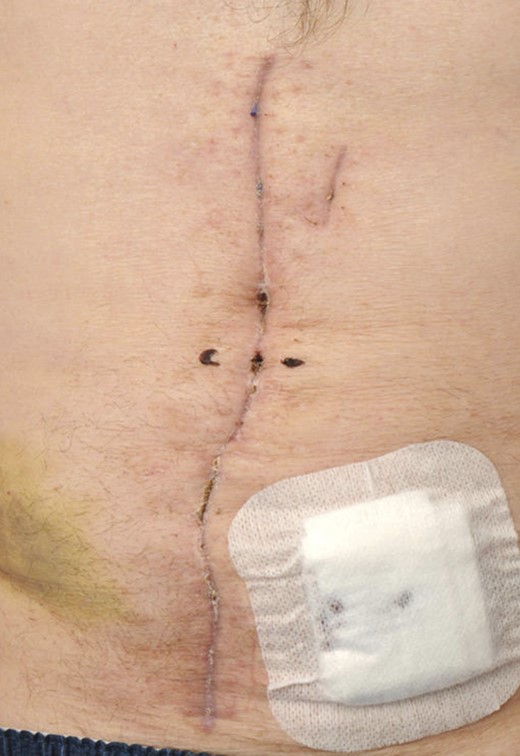

On the 11th postoperative day, a component separation was performed. The topical negative pressure dressing was removed leaving the defect shown with the anterior sheath retracted away from the midline (see Fig. 1) . The overlying skin was released bilaterally from the abdominal wall, and the anterior rectus sheath was released. To achieve this, the external oblique was incised at Point A, and the incision taken high to the costal margin and as low as possible to allow maximal release. The internal oblique is then exposed (Point B), and the released edge is visible at Point C (see Fig. 2).

Defect following removal of topical negative pressure dressing.

On the 16th postoperative day, he suffered a witnessed ventricular fibrillation cardiac arrest. He was resuscitated and subsequently anticoagulated. The following day a computed tomography scan revealed a large abdominal wall haematoma anterior to the rectus sheath. He returned to theatre on the 17th postoperative day. The fascia was found to be intact, and the haematoma evacuated. Topical negative pressure was reapplied. On the 21st postoperative day, the skin was reclosed. He returned to the ward and was discharged on the 49th postoperative day, following implant of a cardiac defibrillator, with an intact wound (see Fig. 6).